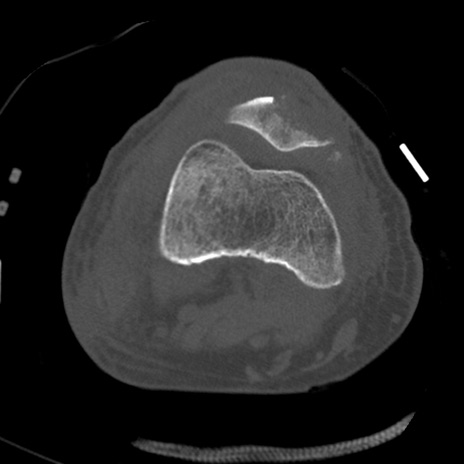

症例28 右膝関節CT(横断像)

右膝関節CT